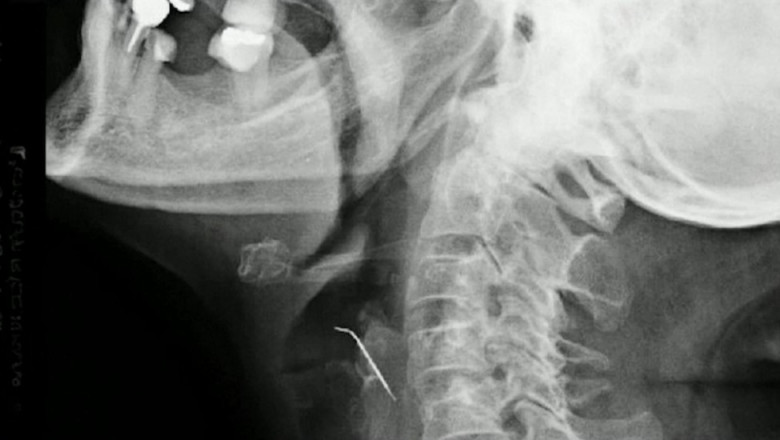

O femeie din Peru, în vârstă de 68 de ani, a ajuns de urgență la spital după ce a înghitit un obiect în timp ce mânca jumări de porc. După 43 de zile, femeia a fost operată de urgență, iar medicii au descoperit un cui lung de 5 centimetri în gâtul acesteia.

Femeia a fost operată imediat, iar medicii au făcut o descoperire șocantă - un cui lung de 5 centimetri în gâtul acesteia, care se afla într-una dintre arterele carotide. Această situație extrem de rară și periculoasă a necesitat o intervenție chirurgicală complexă pentru a salva viața pacientei.

"Ea a fost norocoasă că a ajuns la spital la timp, înainte de a suferi un accident vascular cerebral. Cuiul i-a străpuns artera și putea avea consecințe fatale", a declarat unul dintre medicii implicați în operație.

Intervenția chirurgicală de succes a fost prima de acest tip efectuată în Peru și unul dintre puținele cazuri înregistrate la nivel mondial. Femeia se recuperează acum la spital și este supravegheată de medici pentru a se asigura că nu apar complicații după operație.